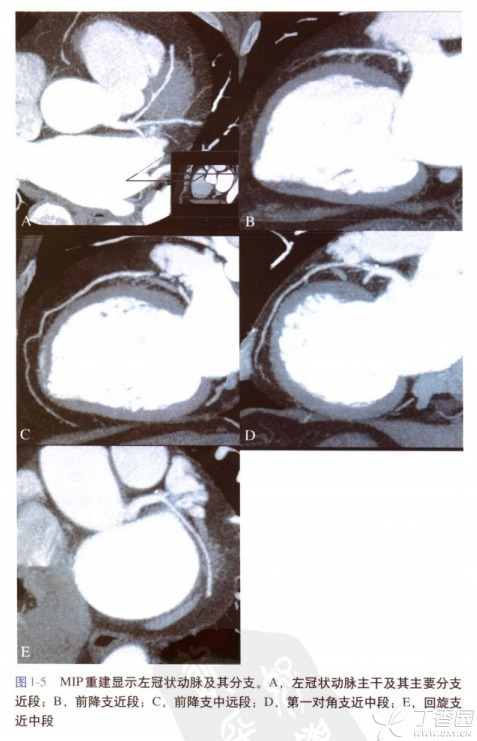

CPR是在一个维度上选择特定的曲线路径,将该路径上的所有体素在同一平面上进行显示,可以一次评价曲度较大的结构如脾动脉、胰管、冠状动脉等管状结构的全长情况,例如图一头颈血管显示。

CPR可以观察管腔结构的腔壁病变(如斑块、狭窄等),也可以观察管状结构与周围结构的位置关系,但CPR所显示的不是正常的解剖结构和关系(它是把管状结构拉直了看,例如图二的冠脉拉直图像),同时需要多个角度曲面重建以完整评价病变。